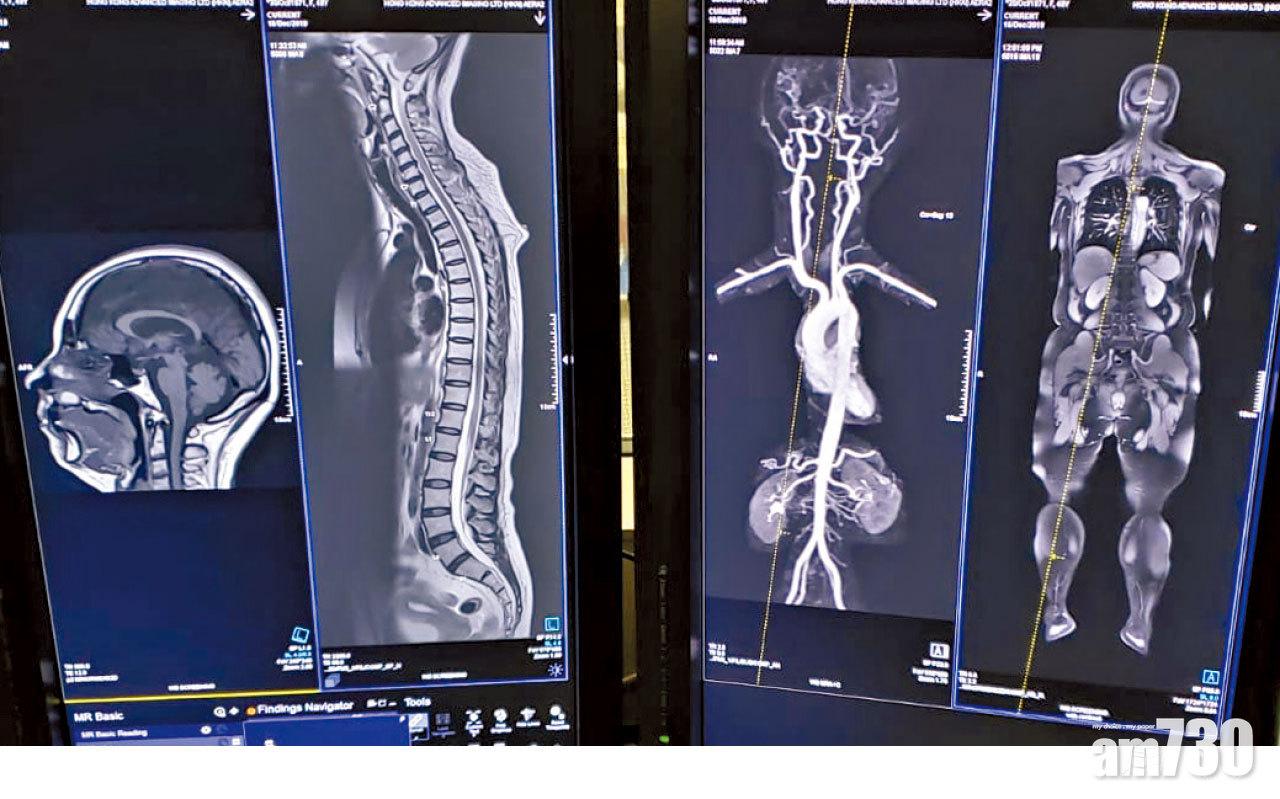

過往,做磁力共振(MRI)檢查多是局部性的,例如頸部、頭部、肺部,甚至心臟磁力共振,一般需時30至45分鐘。但原來,全身磁力共振需時也大約只是45分鐘,由頭到腳一次過「睇晒」,可發現早期癌症、血管收窄等,病向淺中醫。

放射科專科醫生岑承輝表示,全身磁力共振可一次過由頭部掃描至腳跟,唯一不包括雙手,「這是因掃描時雙手的位置問題。其餘可以很全面地掃描全身,由頭頸、鼻咽、胸腔、腹腔以至卵巢、前列腺等都可一次過檢查,獲得病人身體是否隱藏著一些可致命疾病的資訊。」

全身磁力共振可由頭到腳看到血管、脊椎等有否隱藏的健康問題。